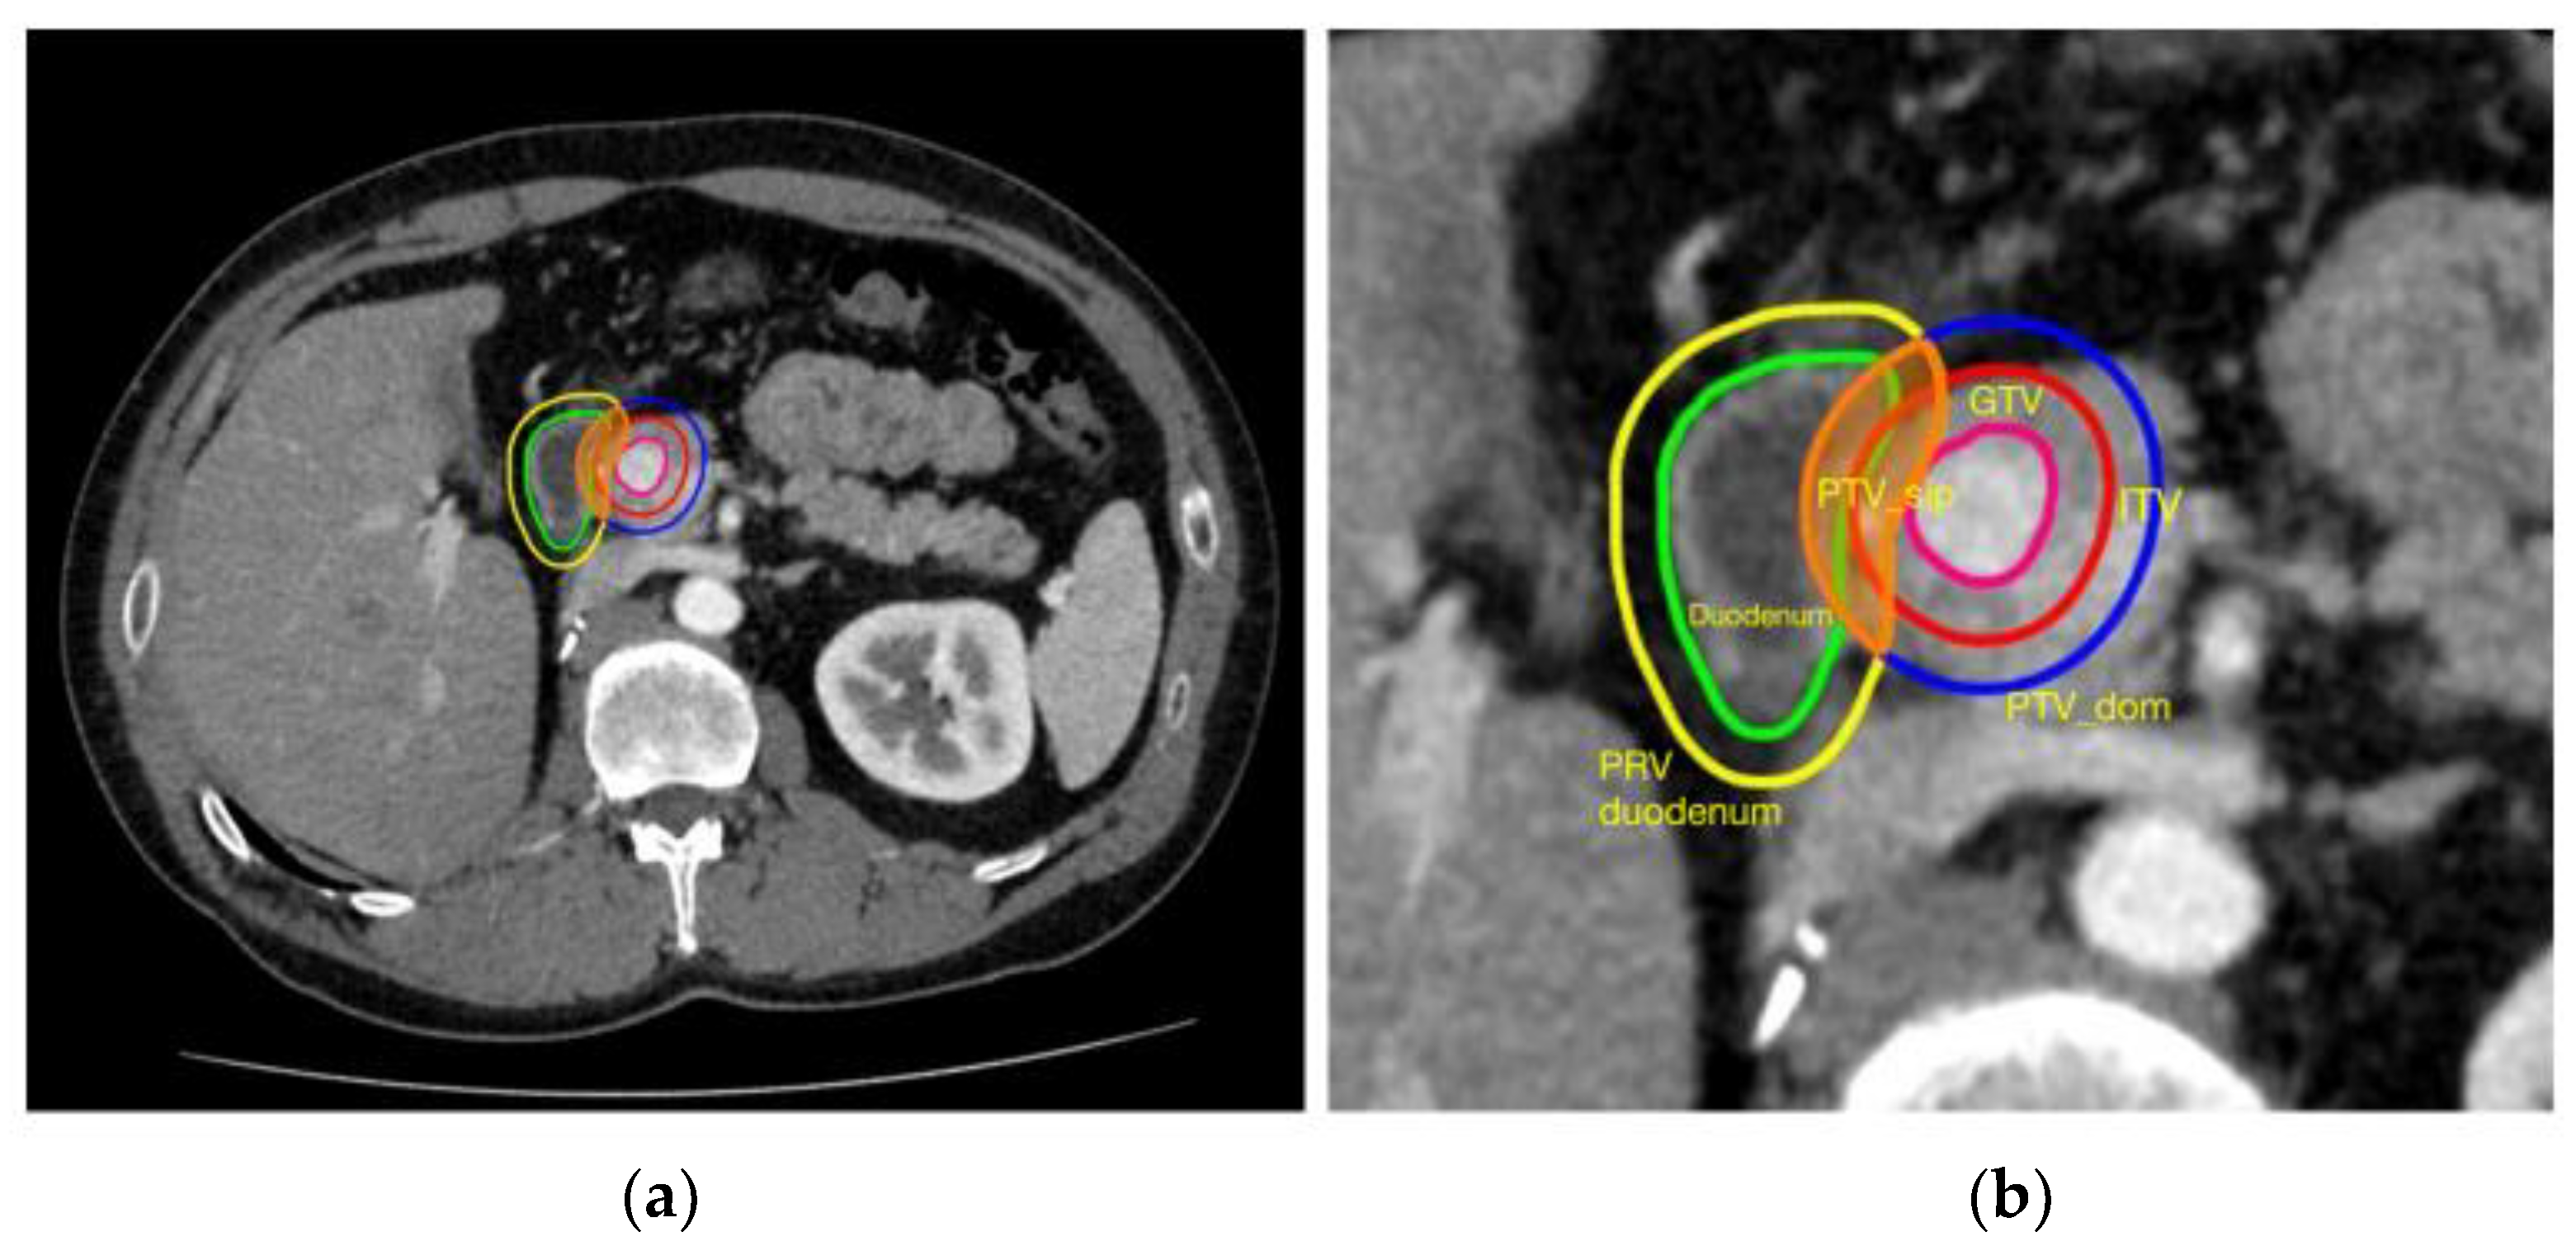

- For use of SIP as planning strategy, the planning process had to be clearly described in material and methods sections; the keyword “SIP” was not necessary, but dose prescription had to be decreased in the area of overlap between PTV and OAR as in the SIP process;

- Simoni, N.; Micera, R.; Paiella, S.; Guariglia, S.; Zivelonghi, E.; Malleo, G.; Rossi, G.; Addari, L.; Giuliani, T.; Pollini, T.; et al. Hypofractionated stereotactic body radiation therapy with simultaneous integrated boost and simultaneous integrated protection in pancreatic ductal adenocarcinoma. Clin. Oncol. 2021, 33, e31–e38. [Google Scholar] [CrossRef]